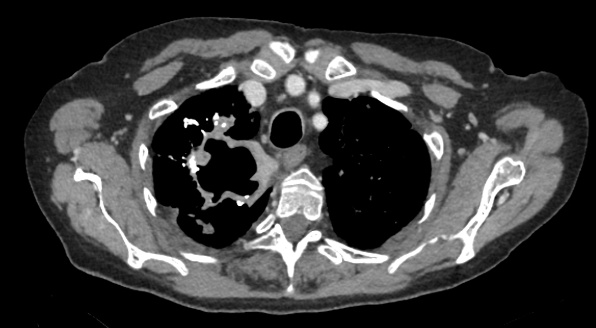

TC de tórax con contraste IV (ventana de mediastino)

HALLAZGOS RADIOLÓGICOS

Lesión apical derecha cavitada con pared gruesa irregular no calcificada, con adenopatías mediastínicas